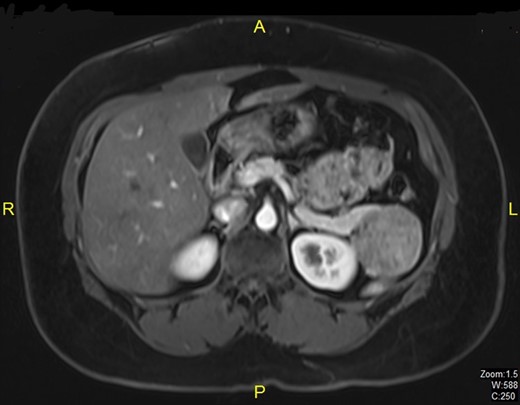

A 38-year-old married woman, who had undergone brachytherapy, radiotherapy and chemotherapy for cervical cancer in the Philippines in the year 2011, was admitted to our hospital after a follow-up CT scan of the abdomen in 2012 revealed a lesion in the tail of pancreas which on subsequent MRI scan was diagnosed as benign intraductal papillary mucinous neoplasm measuring 5.1 × 4.6 cm (Fig. 1). Physical examination revealed no abnormal findings. Tumor markers including CA 19-9 and CA 125 were within normal limits. Cervical smear was negative for malignancy. The patient underwent distal pancreatectomy and splenectomy. Histopathological examination showed solid pseudopapillary tumor of the pancreas (Fig. 2). Postoperatively she developed unilateral lower lobe consolidation. She recovered smoothly and was discharged 8 days after resection.